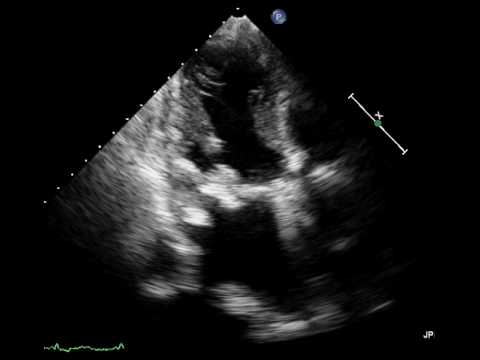

断層法で、僧帽弁尖の肥厚・石灰化、前尖のdoming、弁下組織(腱索、乳頭筋)の肥厚・短縮、弁輪部の石灰化、交連部の癒合などについて観察する。

動画 画像をクリックすると動画が再生いたします

• 僧帽弁狭窄症の重症度評価

:経胸壁心エコー図1

:経胸壁心エコー図2